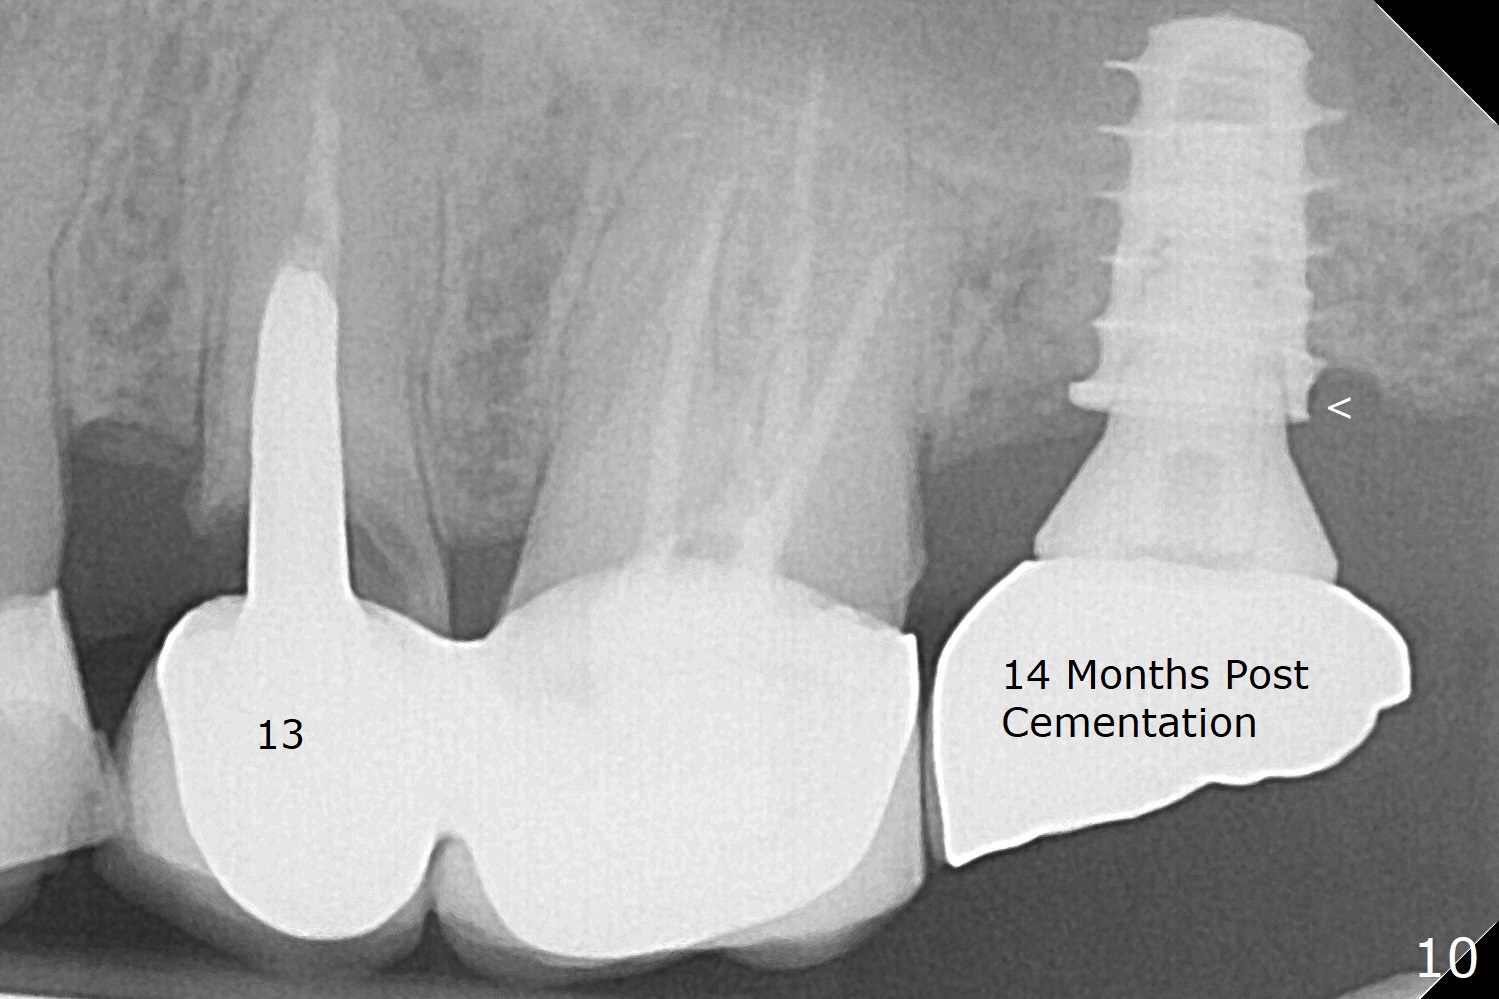

After removal of the mesial (M) and distal (D) residual roots of the tooth #15 (Fig.1,2), Magic Split is used to test bone density (high), followed by Magic Drills from Magic Sinus Lift Kit (for 4 mm) and Magic Surgical Kit (for 5 mm). It appears that the sinus floor has been perforated with the intact sinus membrane. Following minimal use of Magic Lifter, Vanilla Graft is inserted (Fig.3,4 *) and a 4x9 mm dummy implant is placed. After placement of more allograft (Fig.5 *), a 5x7 mm implant is placed with ~ 35 Ncm. With placement of a 5.5x4(2) mm abutment, an immediate provisional is fabricated to close the socket. Six months postop, the bone graft remains in the sinus around the apical end of the implant (Fig.6 *), while there seems no bone loss coronally (Fig.7). In fact there is, as shown later (Fig.8-11 < and lingual (L)). The crown is recemented 6 months post cementation (due to short abutment). The abutment seems to be incompletely seated. When the crown at #14 is reprep following #13 implant, the abutment screw is being untightened, the crown dislodges first. The abutment is confirmed short with more than enough occlusal clearance. After use of 5.5 and 6.0 mm bone profile drills, a 5x4(3) mm abutment is placed with complete seating.